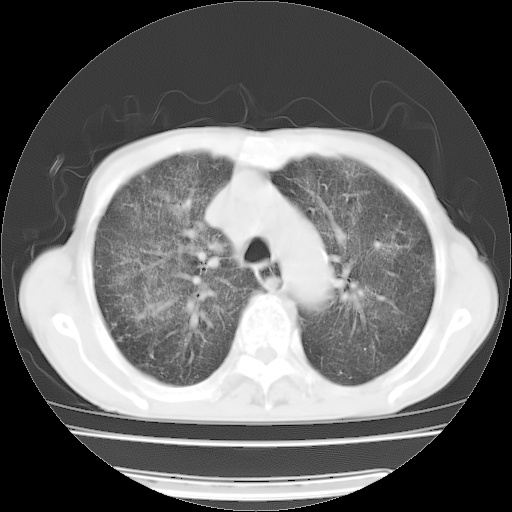

病人发热、气促就诊。原二周前已行ct扫描,当时诊断为双肺下叶、右肺中叶支气管扩张并感染,双肺上叶片状渗出性病变。今天复查胸部ct,双肺下叶支气管扩张并感染病灶较前明显吸收,但双肺上叶渗出性病变较范围较前明显增大。

现传今天ct图像给大家讨论。

双肺多发大片状、斑片状高密度渗出影,部分实变,考虑病毒性肺炎。